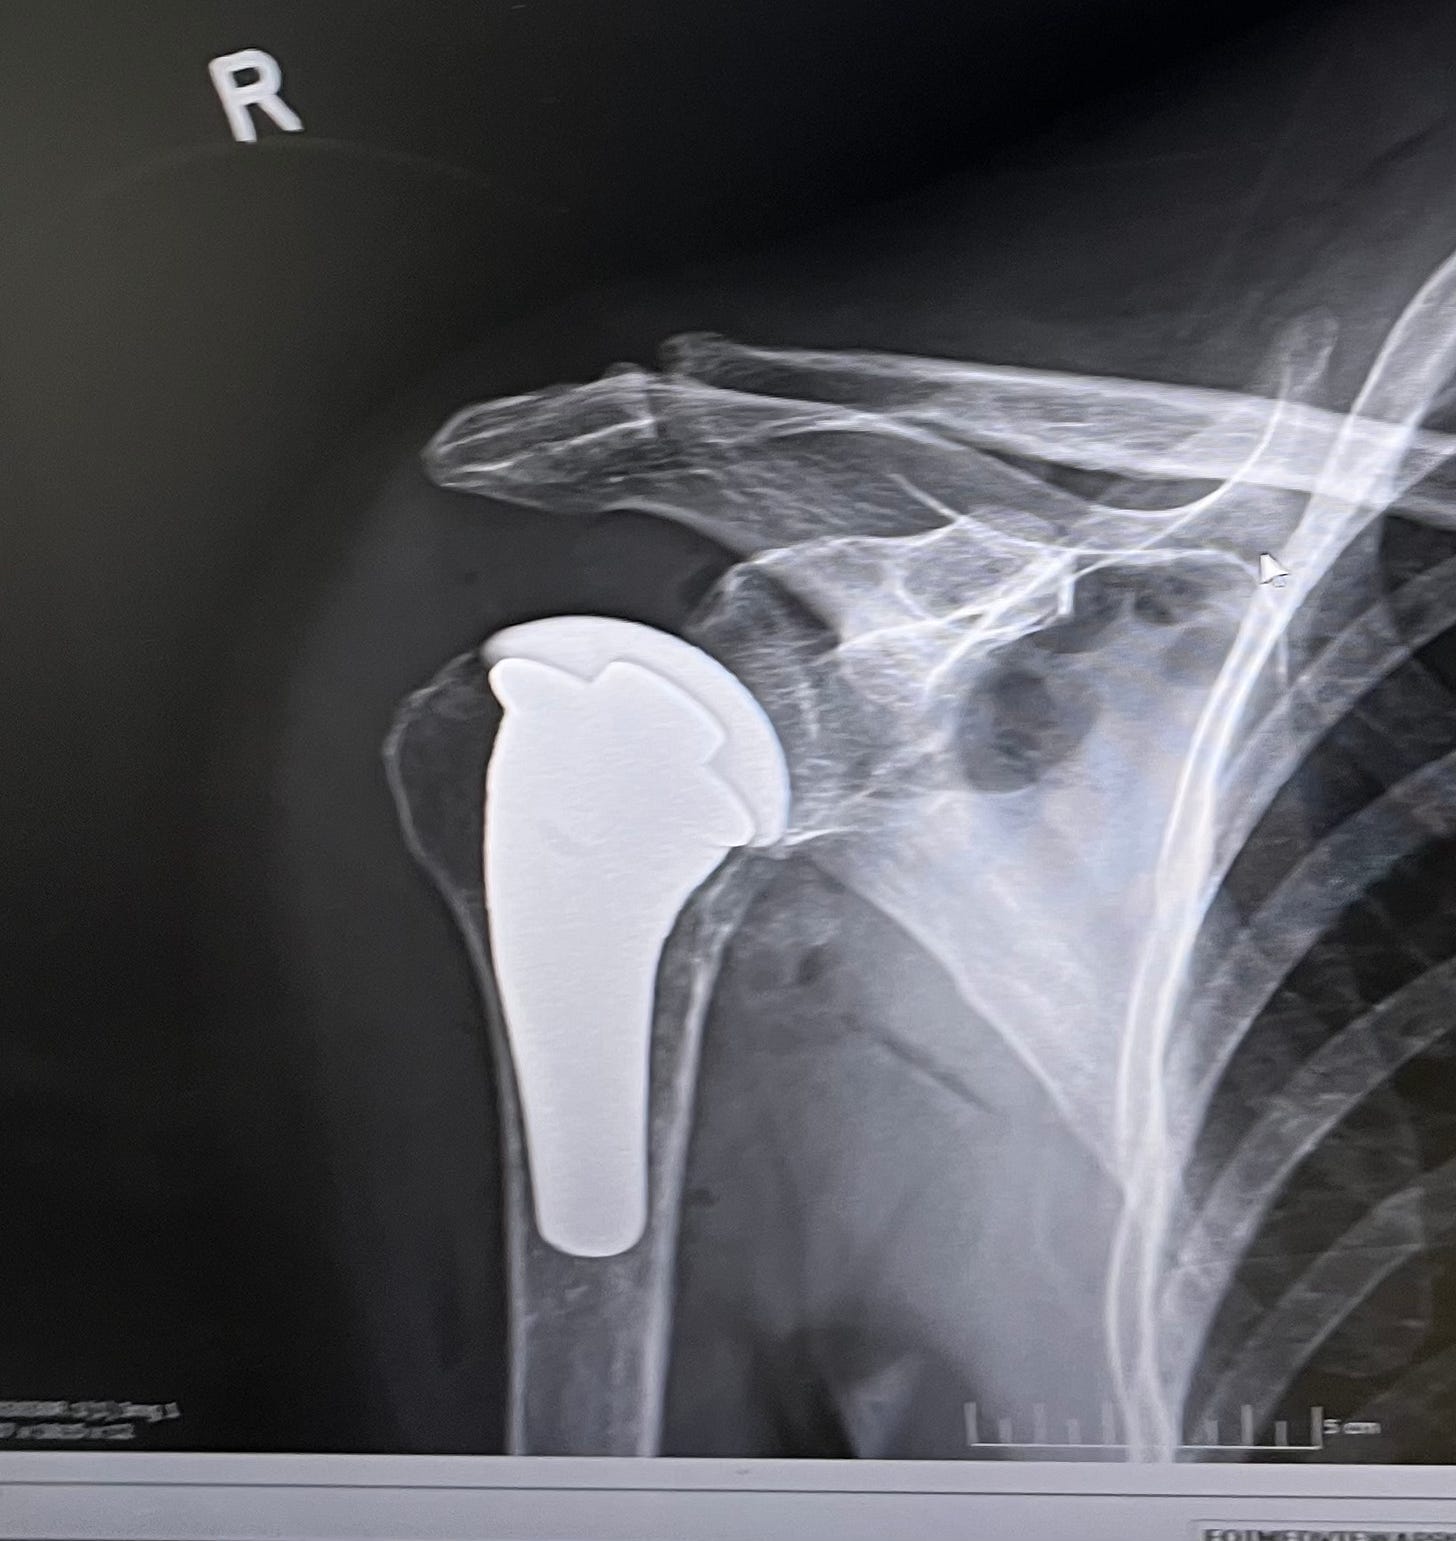

About hemiarthroplasty of my right shoulder

My right shoulder had been getting worse for 15 years. I tried all the alternatives from cortisone to turmeric, Tai chi to yoga, glucosamine to fairy dust, and there was no magical cure for bone-on-bone arthritis. X-rays don’t lie. Despite daily PT, stretching, resting, etc, the joint was only getting worse. I could no longer move my right arm to swim the crawl. I couldn’t put my hand behind my back past my hip. It was time for a new shoulder joint.

Like the word semi, “hemi” implies that only part of the joint is replaced, the ball part. I googled shoulder replacements and found a peer-reviewed meta analysis showing that total shoulder replacements (new ball and socket) had better outcomes than hemis. I freaked out. I told Rita that a total sounded much better than a hemi.

We were watching manatees when Dr. Mighell called. He explained that those studies didn’t include hemis with the pyrocarbon head he would use. This new technology has a 95% success rate, so forget those other stats, he said. OK, he’s the man. Fingers crossed.

Dr. Mighell replaced the head of my humerus, the ball joint, with a pyrocarbon bearing. Here’s the joke: It was “cutting edge” science in the world of surgery.

I can’t open the car door or close it. I can’t drive. Tampa traffic is a panic. Tony does everything. We meet Dr. Mighell who is happy with his work and my recovery. I can wiggle my fingers, pump my fist, rotate palm up, palm down, and wave my hand that feels like a flipper. He shows us an X-ray of my hemi and we take a photo with my phone (below).